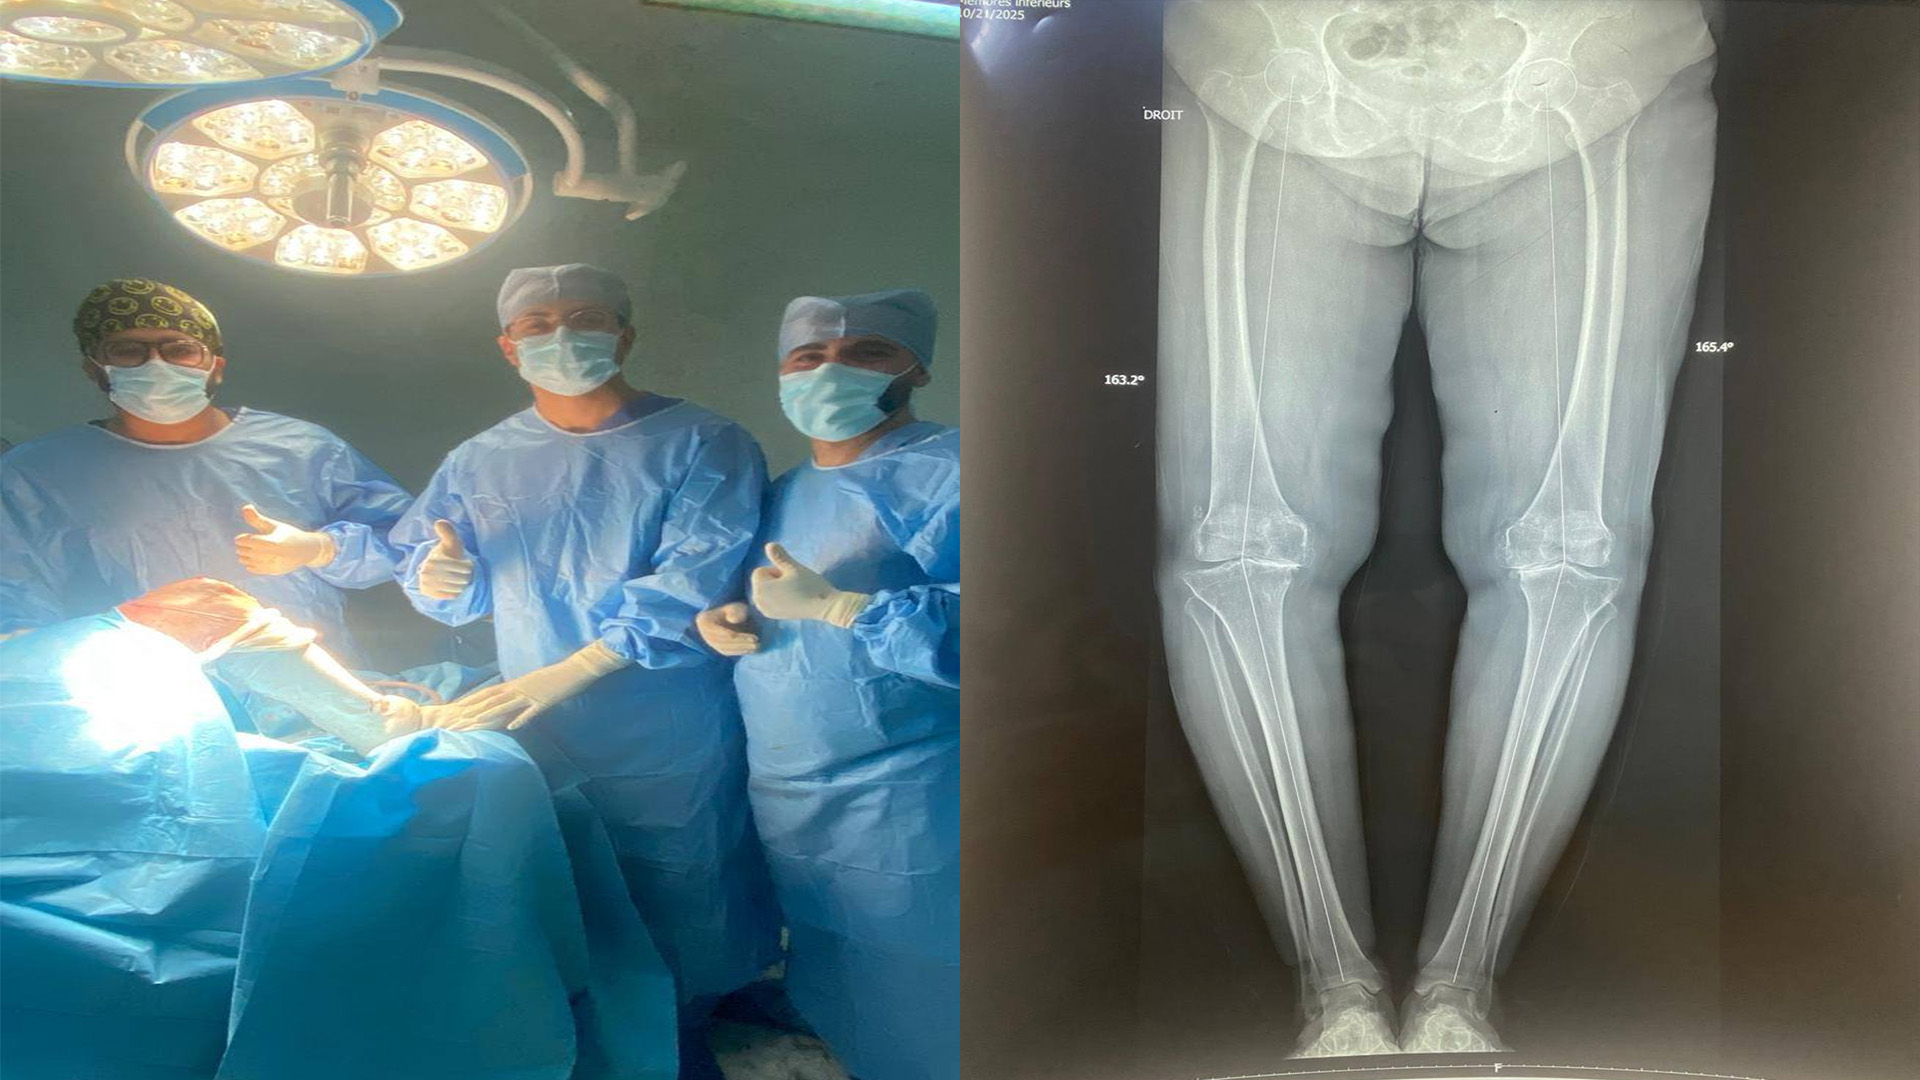

أعلنت وزارة الصحة عن إنجاز طبي جديد بالمناطق الداخلية، نجح فريق جراحة العظام بالمستشفى الجهوي بجندوبة في إجراء عملية تركيب مفصل اصطناعي كامل للركبة (Prothèse totale du genou) لمريض يعاني من تآكل متقدم في مفصل الركبة.

وقد أُنجزت العملية تحت إشراف الدكتور سيف الدين محجوبي وبالتنسيق مع فريق التخدير والإنعاش، حيث تكللت بالنجاح ومكّنت من إعادة هذا النوع من الجراحات الدقيقة إلى المستشفى بعد سنوات.

ويعكس هذا الإنجاز تطور الخدمات الجراحية بالمؤسسات الصحية في الجهات وكفاءة الإطارات الطبية، في إطار حرص وزارة الصحة على تدعيم المستشفيات الجهوية بالتجهيزات الحديثة وتطوير الاختصاصات لتقريب الخدمات الصحية المتقدمة من المواطنين.